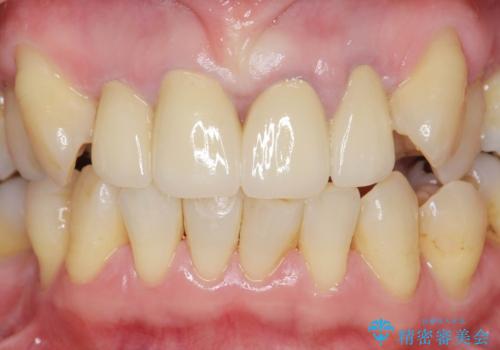

オールセラミックによる審美的な仕上がりに満足いただくことができました。

前歯の見た目をオールセラミッククラウンで改善